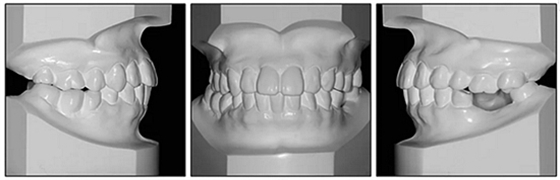

36歲;女性;尋求下頜左后方區(qū)域間隙管理的建議(圖1和圖2),通過(guò)治療獲得了良好的牙頜面效果(圖3和圖4)。她被診斷患有骨性I類和代償性牙性II類錯(cuò)合畸形,并且上頜左側(cè)尖牙缺失(圖1和2)。大約七年前,由于不可修復(fù)的齲齒,拔除了下頜左側(cè)第一和第二磨牙(圖5)。37相鄰的第三磨牙向近中移動(dòng)并傾斜入間隙,導(dǎo)致無(wú)牙頜間隙減小至約14 mm(圖2和圖5)。臨床和影像學(xué)評(píng)估顯示多發(fā)性齲損和在下頜右側(cè)567處有一不良的固定橋修復(fù)體(圖1和5)。此外,下頜左中切牙缺失,造成下頜中線向左側(cè)偏移約3 mm(圖1和圖2)?;颊咦栽V,她的右上第一前磨牙和左上尖牙在13歲時(shí)由其家庭牙醫(yī)拔除,因?yàn)樗鼈儽蛔枞筋a側(cè)萌出(圖1)。上頜第二磨牙缺失(未知病因),并且相鄰的第三磨牙已經(jīng)轉(zhuǎn)移到第二磨牙間隙中。如補(bǔ)充材料所示,美國(guó)正畸學(xué)差異指數(shù)DI是28分。種植體部位(下頜左側(cè)和右側(cè)第一磨牙)由于復(fù)雜性得到額外4分(補(bǔ)充材料)。

圖1. 治療前面部和口內(nèi)照片

圖2. 治療前牙齒模型